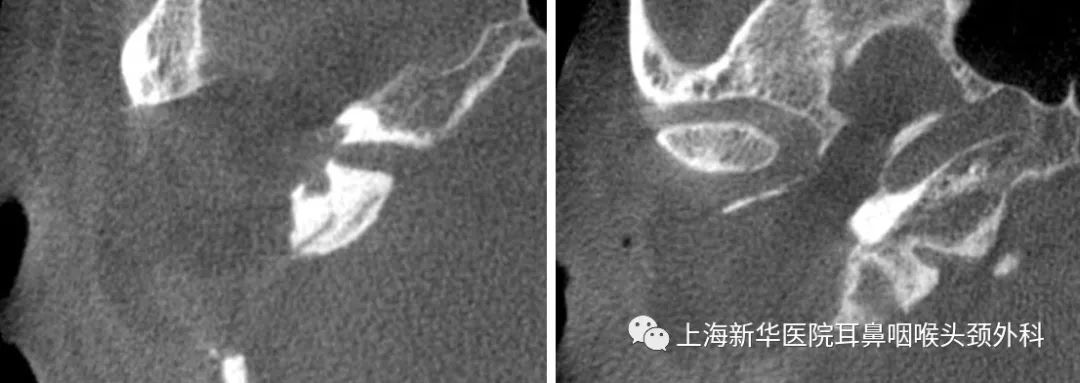

影像学检查:

术前CT